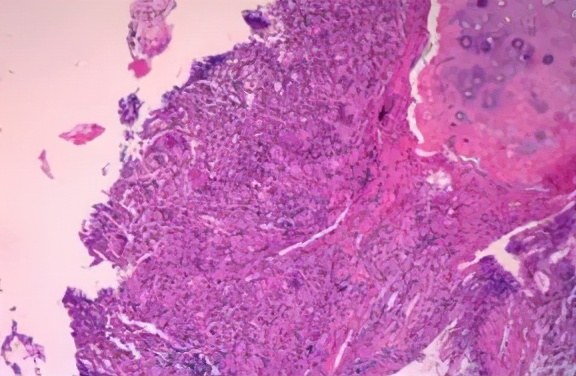

综合分析原因有两种可能性,一是抗生素未覆盖致病菌,二是非细菌感染或者非感染性疾病所致。但考虑患者生命体征平稳,未升级抗生素,而是进一步寻找病因:完善纤维支气管镜检查,镜下见气管及各级支气管粘膜光滑,管腔通畅,可见少量粘稠分泌物,抽取分泌物送细菌培养,并0.9%生理盐水灌洗右下叶背段支气管,留取灌洗液送检真菌GM试验、抗酸染色、弱抗酸染色、真菌涂片及病原学mNGS,于7组淋巴结行EBUS-TBNA,于右下叶后基底段支气管行EBUS-TBLB。结果回示真菌GM试验、抗酸染色、弱抗酸染色、真菌涂片均阴性;7组淋巴结穿刺细胞块病理回示渗出背景上少量淋巴细胞,右下叶TBLB肺活检示肉芽肿性炎(图3),抗酸染色(-),PAS(-),六胺银(-),TB-DNA(-)。

图3:(右下叶活检)肉芽肿性炎,抗酸染色(-),PAS(-),六胺银(-),TB-DNA(-)

右下叶EBUS-TBLB回示肉芽肿性炎,考虑结核,支持点:病程无发热,肺部影像学表现为多形性病变,活检病理回示肉芽肿性炎;不支持点:病情进展迅速,病理组织抗酸染色及TB-DNA均阴性,血清TSPOT阴性,多次送检痰及支气管肺泡灌洗液抗酸染色阴性。